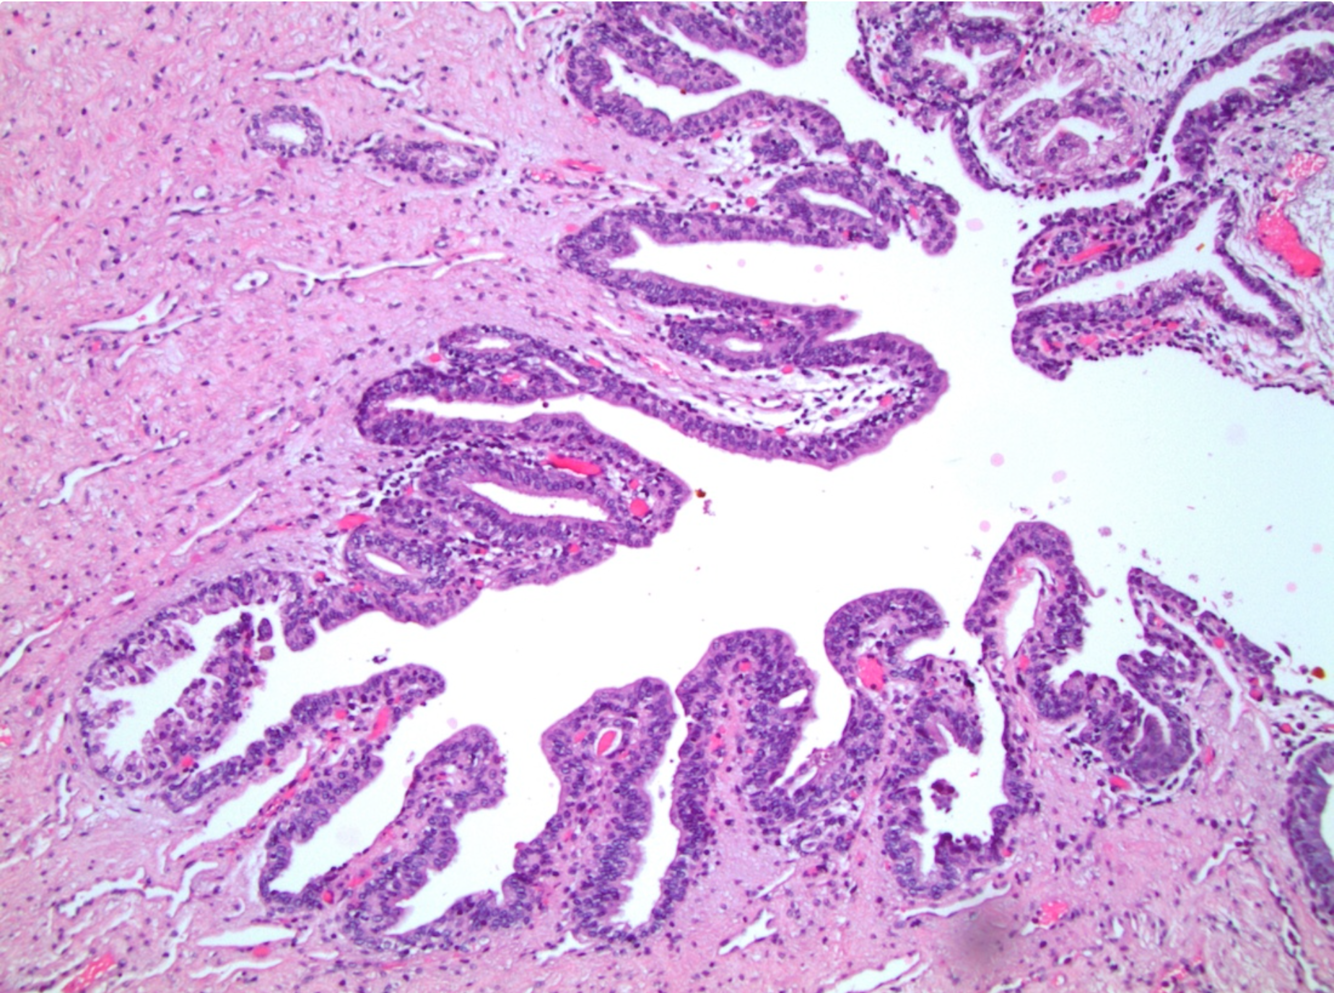

What is this showing?

Epithelium of the fallopian tube

ciliated columnar epithelium